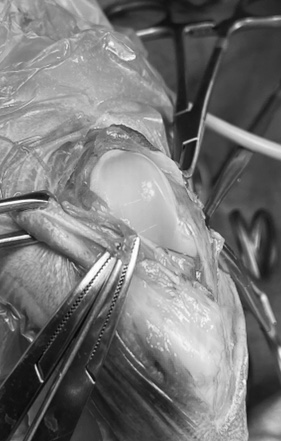

術中写真は大腿骨の滑車溝を深くするための造溝術の様子です。

当院では犬では四角くブロック状に骨を切って溝を造るブロック法で行いますが、猫では骨のかたちや硬さを考慮し、楔形に切るウエッジ法を採用することが多いです。